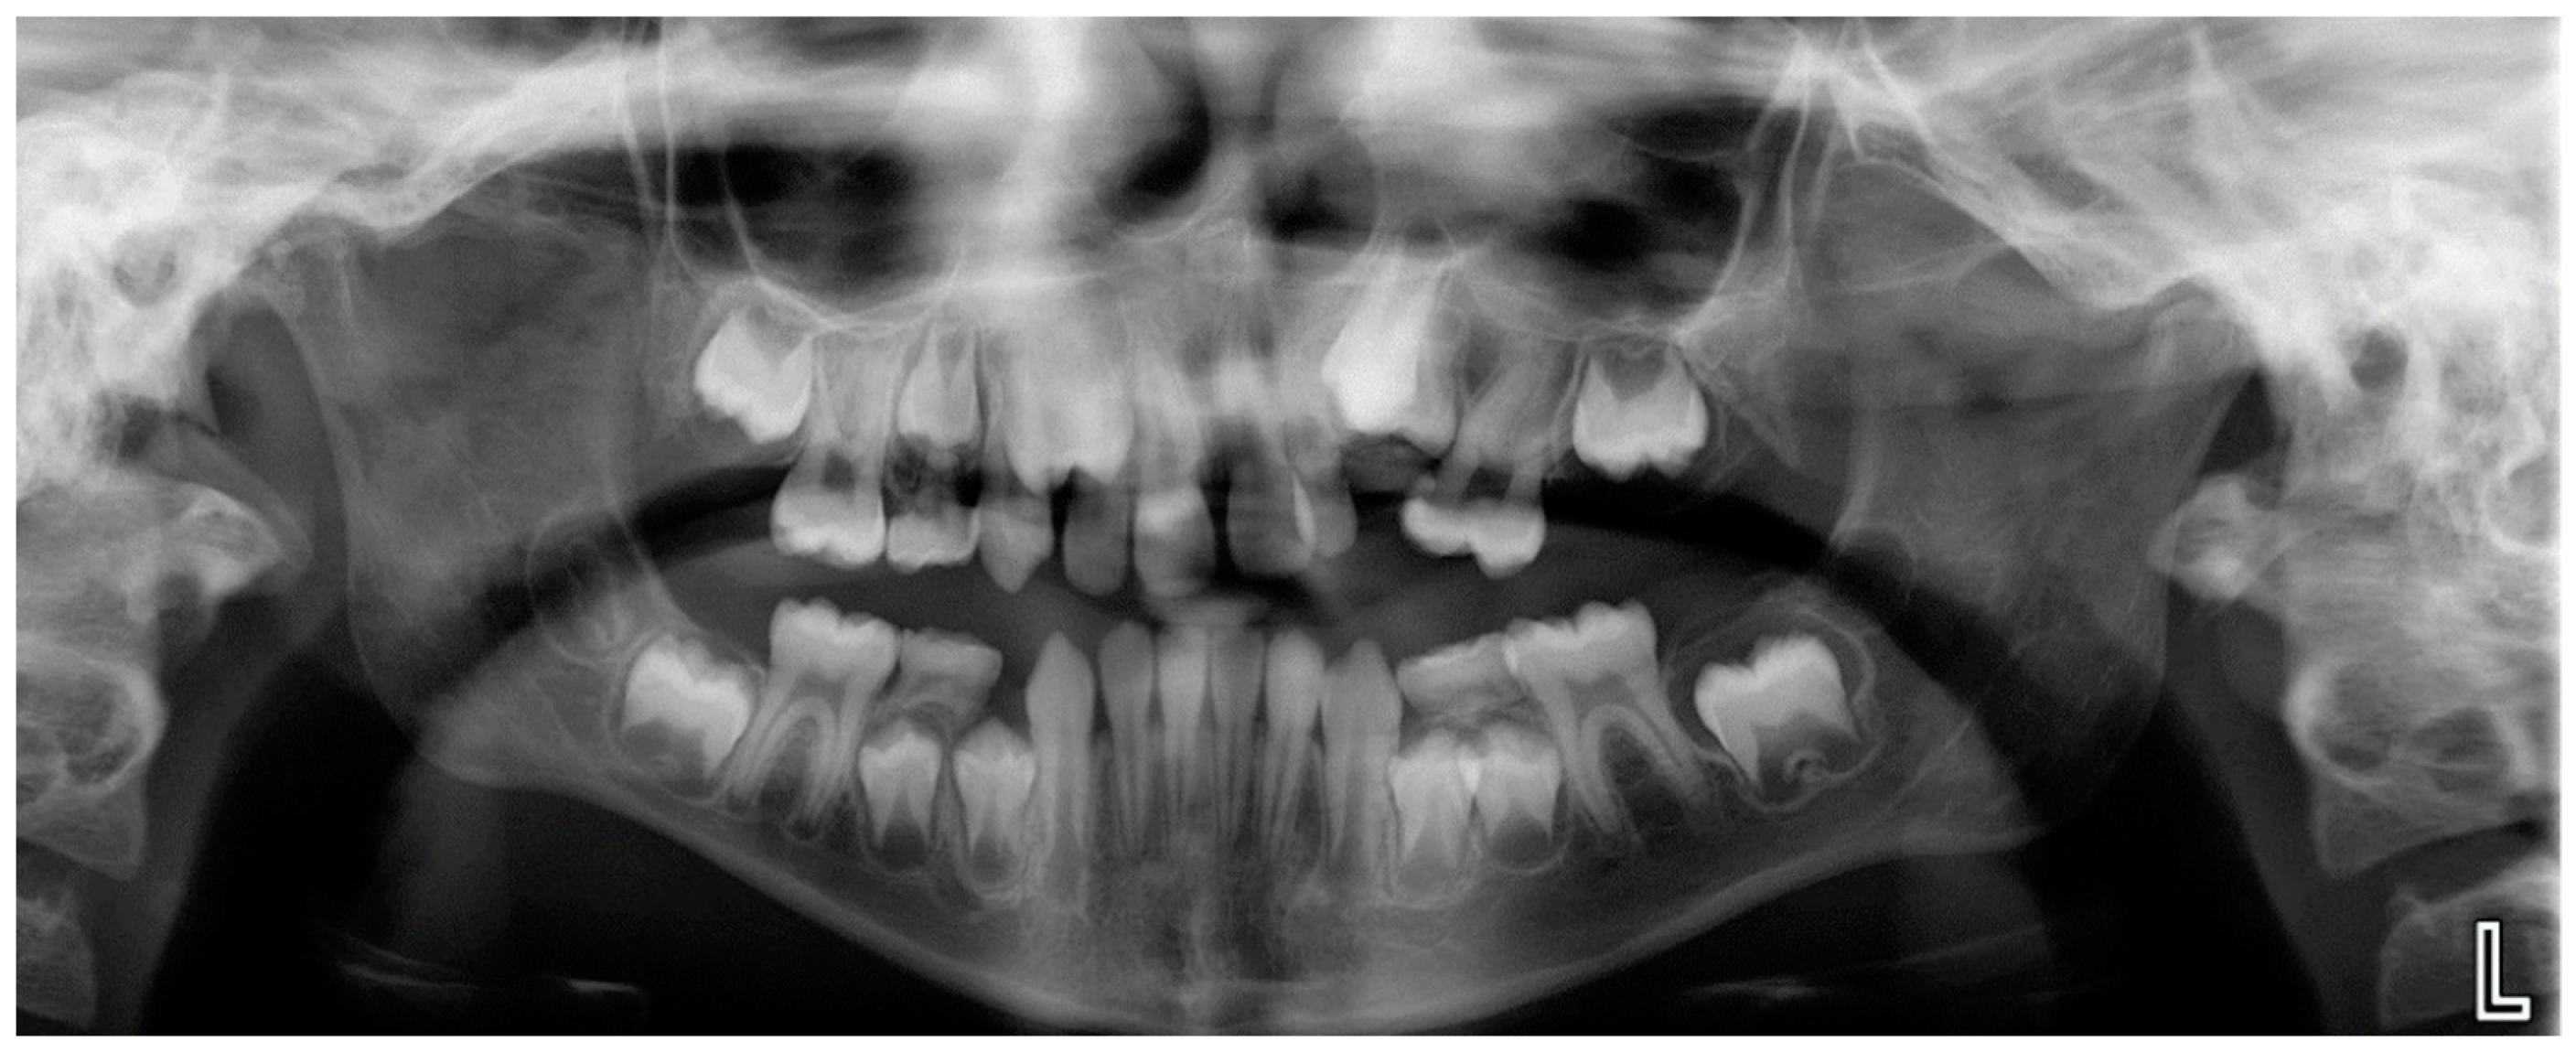

- Evaluation of impacted teeth, a common indication of CBCT in orthodontics. The advantages of CBCT include assessment of the tooth location and position, the stage of development, and status of adjacent teeth. CBCT is justified in these cases, because CBCT has the capability of evaluating the impacted teeth and adjacent structures more accurately than 2D conventional imaging. The benefit–risk ratio is favorable, especially if the CBCT volume is collimated to the impacted tooth. Figure 1, Figure 2, Figure 3 and Figure 4 show an example of impacted maxillary canines, and their proximity to the maxillary lateral incisors. Figure 1 shows an intraoral photograph. The benefit of CBCT acquisition in this case includes the ability to visualize the canines and the lateral incisors in three dimensions, which can be visualized in Figure 2 and Figure 3. In this case, the maxillary right lateral incisor exhibited external root resorption, a finding that would be difficult to see on a conventional 2D panoramic radiograph. Figure 4 shows a Maximum Intensity Projection of a panoramic view derived from the CBCT volume. This unique view is free of magnification, distortion, ghost images, and overlaps frequently seen in conventional 2D panoramic radiography.